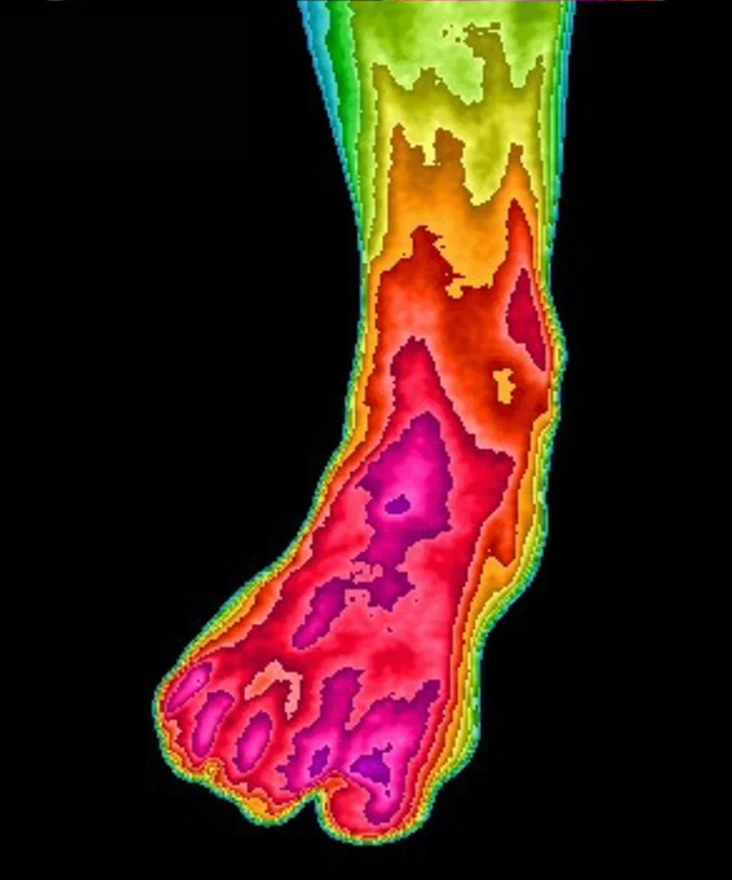

Built for Maximizing Your Health Benefits

We engineer every product for maximum electron flow—because when grounding is done right, you can feel the difference. Real grounding delivers measurable benefits like less inflammation, deeper sleep, reduced stress, and faster recovery—and we never cut corners to get you there.